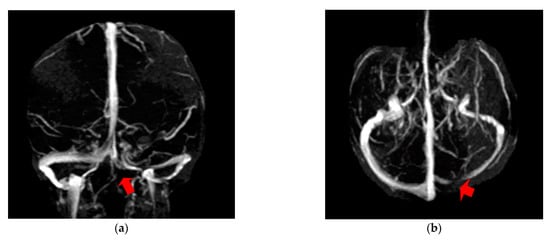

The first case, was a female, 26 years old, with an etiology of left otomastoiditis, hospitalized in superficial coma, with meningeal symptoms and HIC, psychomotor agitation and three generalized seizures. The Grisinger sign was present at local examination of mastoiditis. After a period of six months, at the reevaluation, the same patient did not present any residual symptomatology related to thrombophlebitis. The imagistic features can be seen in Figure 1 and Figure 2.

Figure 2. MR- venography 2D-TOF (2D- time of flight) in the coronal (a) and axial (b) plane reveals permeabilization of the left lateral sinus after six months from the onset.